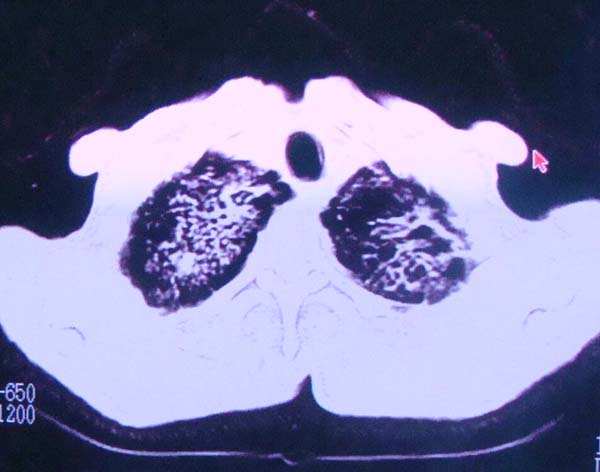

以下是引用zhangzhongshou在2008-2-15 22:25:00的发言:[br]片子照得不清,基本考虑1、细支气管肺泡癌2、亚急性血行播散型肺结核。请结合临床。片子细节显示不清,无法提供进一步意见。

以下是引用杀毒软件在2008-2-15 22:34:00的发言:[br]小叶中心性肺气肿。两肺弥漫性病变,肺泡微石病,过敏性肺炎,尘肺2期,特发性肺纤维化都有可能。[br]不象肺泡癌。